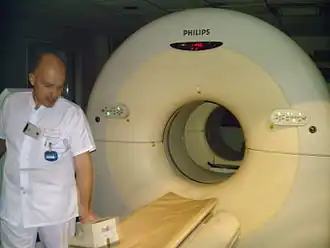

Ce n'est qu'à partir des années 2000 que les premiers scanners multi modalité TEP/TDM couplant au sein du même statif un scanner à rayons X (tomodensitométrie, TDM) avec un scanner TEP sont construits puis commercialisés[5]. Ces machines sont dorénavant le standard de référence, les grands constructeurs (Philips, Siemens et GE) ne fabriquent plus que ce type de machine et la quasi-totalité des services cliniques utilisent des machines multi-modalité TEP/TDM.

Lors de l’examen, le patient est allongé sur un lit qui se déplace à l’intérieur d’un anneau détecteur. Seule une partie du corps se trouve à l’intérieur de l’appareil. De ce fait, les patients claustrophobes ne ressentent en général aucune gêne particulière au cours de l'examen. De plus, la machine est silencieuse, contrairement à l'IRM. L’enregistrement des images dure de 20 à 40 minutes selon les machines ou l'indication de l'examen. Au total, le patient doit prévoir de rester dans le service environ 2 à 3 heures pour l’ensemble de la procédure. Un premier avis peut être donné par l’équipe médicale sur place mais le compte rendu détaillé de l’examen nécessite un délai plus long. Après l’examen, il est recommandé de bien boire afin d’éliminer le plus rapidement possible le traceur et ne pas se retenir avant d’uriner.